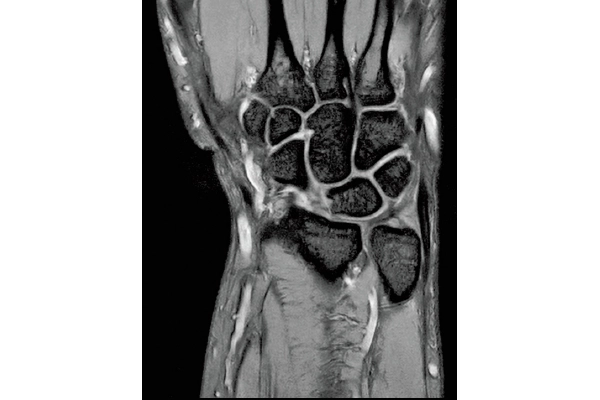

T2*WI Multi Echo,

0.38×0.38×2.0mm

0.35×0.40×3.0mm, 2:55